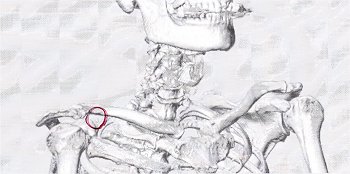

数日前に右腕に激痛が走り、慌てて主治医行きとなりました(^-^;

数日前でしたか…右腕に何となく違和感を感じておりましたが、別に気に掛けておりませんでしたGONsanです。

が、翌日には激痛が走り慌てて主治医行きとなりました(^-^;

とりあえずCTスキャン。

で、頂きましたのが、その一部のこれらの画像なんです(^.-)☆

特に痛みの原因となるようなモノは見当たらず、強いて言えば『老化現象』との事でありました。

痛み止めとシップ薬で痛みが取れなければ、次はMRIとの事でありました(^-^;

…と、こんな記載がWEB上にありましたけど、痛みが取れませんから渋々MRI検査も受ける事に致しました。

と言う訳で、本日がそのMRI検査の実施日でありました。